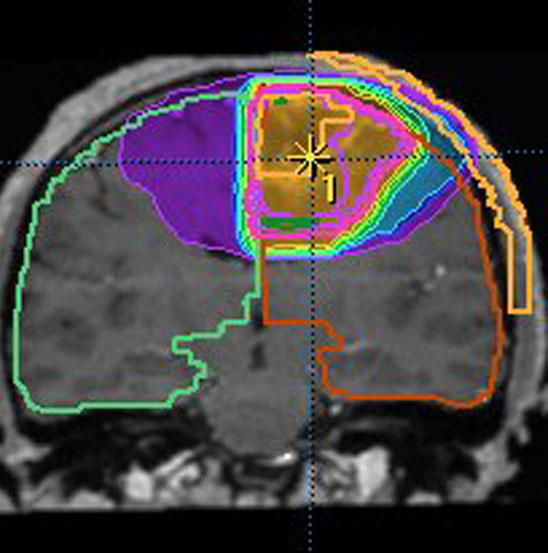

放射線治療計画の等線量曲線 isodose curves です

腫瘍とその周辺にどの程度の線量(グレイ)を当てるかを計画します

赤紫の線で囲われた部分が,実際に計画線量をかける部分(照射野,PTV)です

グリオーマでは,MRIでみえている腫瘍範囲よりかなり広い領域の正常脳にも放射線がかかります

放射線治療計画(照射野)と脳にあたる放射線の量の簡単な図での説明

MRIでみえる腫瘍の領域を腫瘍体積 (GTV)といいます

これは退形成性星細胞腫グレード3のフレア画像と言います。白く見える部分が腫瘍なのですが,どこまでが腫瘍なのかMRIでもわかりにくいものです

オレンジの色がGTVではっきり腫瘍と断定できるところです

グリオーマはMRIでみえる以上に広がっているので,腫瘍の周囲を十分に囲む領域を照射します,それを臨床的標的体積 (CTV)といいます

赤紫の線で囲った部分の内側で,びまん性グリオーマの場合は,GTVから20mmくらいの距離を取るのが普通です

さらに少し (0.3-0.5cm) 領域を広げてかけ損じのないようにするので治療計画表的体積 (PTV)といいます,上の図では赤紫の2本の線の外側にあたります

薄茶色に塗った部分には計画54グレイの90%以上の線量が入ります

この体積の決め方は腫瘍の形や悪性度によっても変わってきます

放射線治療医の腕の見せ所です

実際に放射線があたるのはPTVの領域です

この例の治療計画でとても大切な点は,腫瘍のある左前頭葉には放射線が十分入っているのですが,右前頭葉の被曝は最低限に抑えられている点です

両側の前頭葉の対照的な被曝では認知機能が著しく低下することを知っている放射線治療医だからできることです